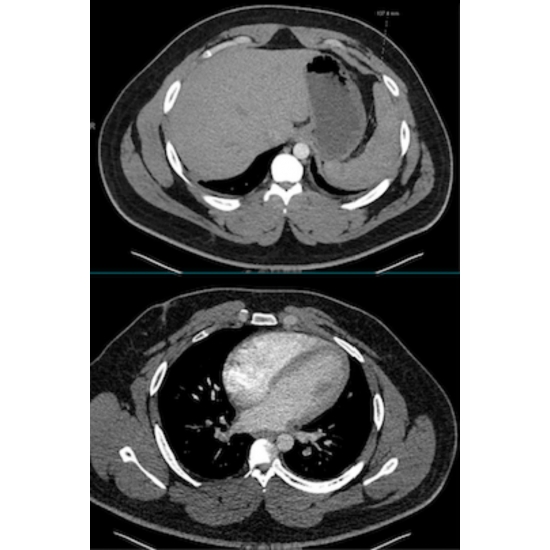

| Delayed Diagnosis Of Atypical Rib Pain In A College Athlete: A Case Report - Page #3 | |||